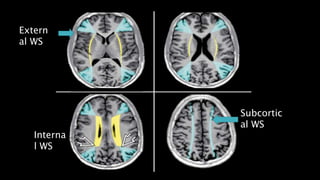

WATER SHED / BORDER ZONE

ExternalWS(MC ,embolic):

InternalWS(by regional hypoperfusion)

Extern

al WS

Subcortic

Interna

l WS

(often reffered to as “ man in

the barrel distribution of

weakness)

• #110 External –wedge or gyriform internal- rosary like line of WMHs

• #111 This is the diagram to show watershed zones .wedge shaped area between ACA , MCA and MCA – PCA represent external watershed zones. Curved blue line represent subcortical watershed zones. Yellow line indicate internal watershed zone b/w major vessels and perforating arteries.

• #112 here is case of watershed infarct FLAIR AXIAL MRI images shows bilateral areas of hyperintensity , most prominent are located posteriorly on the watershed b/w MCA –PCA and also bwtween ACA –MCA watershed in the last 2 images.

• #113 As we saw in THIS example. The image shows typical man in the barrel phenotype with atrophy of shoulder gilde muscles and arms hanging flaccidly .